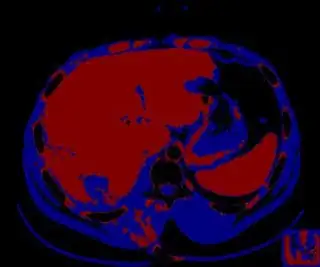

Update

You might be able to narrow down the region or interest by filtering out the darkest and the lightest regions from the segmented image. For this, use the k-means cluster centers, check for the extreme values (max and min) and remove the corresponding k values from the labeled image. Then you can look for large structures to the left of the result image. Worst case, you might get a hole on the left side when the extreme region filtering goes wrong. I've updated the code and results.